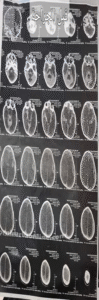

تفريغ ناجح لنزيف دماغي يُنقذ مريضًا سبعينيًا من خطر الموت

كما استقبلت طوارئ المستشفى مريضًا سبعينيًا بسيارة الإسعاف وهو في حالة حرجة ودرجة وعي منخفضة مع ضعف بالجانب الأيمن من الجسم.

أظهرت الأشعة وجود نزيف مزمن تحت الأم الجافية بالمخ، وعلى الفور تم إجراء عملية تفريغ ناجحة، نُقل المريض بعدها إلى العناية المركزة في حالة مستقرة.